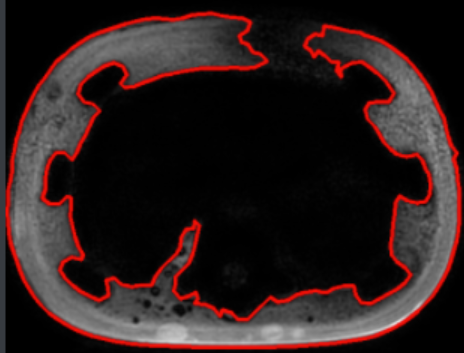

以上是预处理的大致步骤,记得当时寻找轮廓时遇到一个问题,

比如上图,外面的红色轮廓在绿色竖线部分是有缺口的,所以外面的轮廓就不完整,恰好里面绿色轮廓完整,而且和外面”不粘连“,所以扫描出来的结果最大轮廓是里面的轮廓。如下图所示:

这里当时是通过在模糊处理之前加一个(7*7)的闭运算解决的。通过这个闭运算,内外部分会粘连到一起,不会出现完全分隔开的情况。根据开闭运算的原理,闭运算确实能填补内部的一些缝隙,而开运算则能消除内部的一些噪点,小黑洞,如下面两幅图: